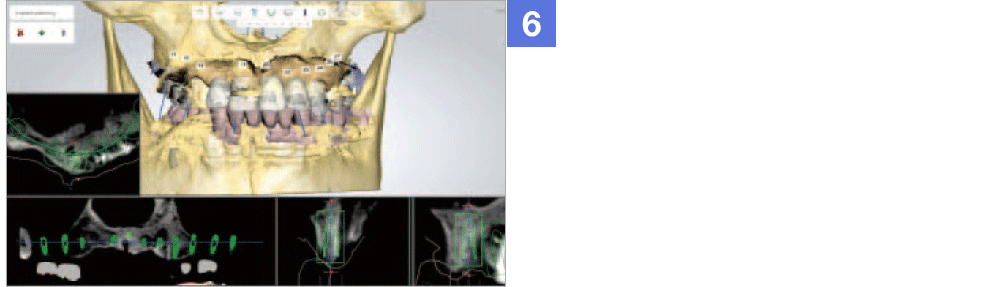

Through virtual operation procedure though 3D computer, DIO NAVI system decreases danger of implant surgery by checking patient's bone tissue and nerve position for planning the optimal surgery procedure and making customized surgical guide.

Not only the mock implant surgery plan that considered the occlusion and stress dispersion, but 3D simulation that can be used as a counseling material for the patient is provided. The doctor can establish a satisfactory treatment plan and with a provided surgical guide, He can operate a safe and accurate procedure.

Through implant planning that considered occlusion and stress dispersion, DIO NAVI Digital Implant System increases the accuracy of the implant treatment and enabled 3D simulation that is used for patient counsel purposes.